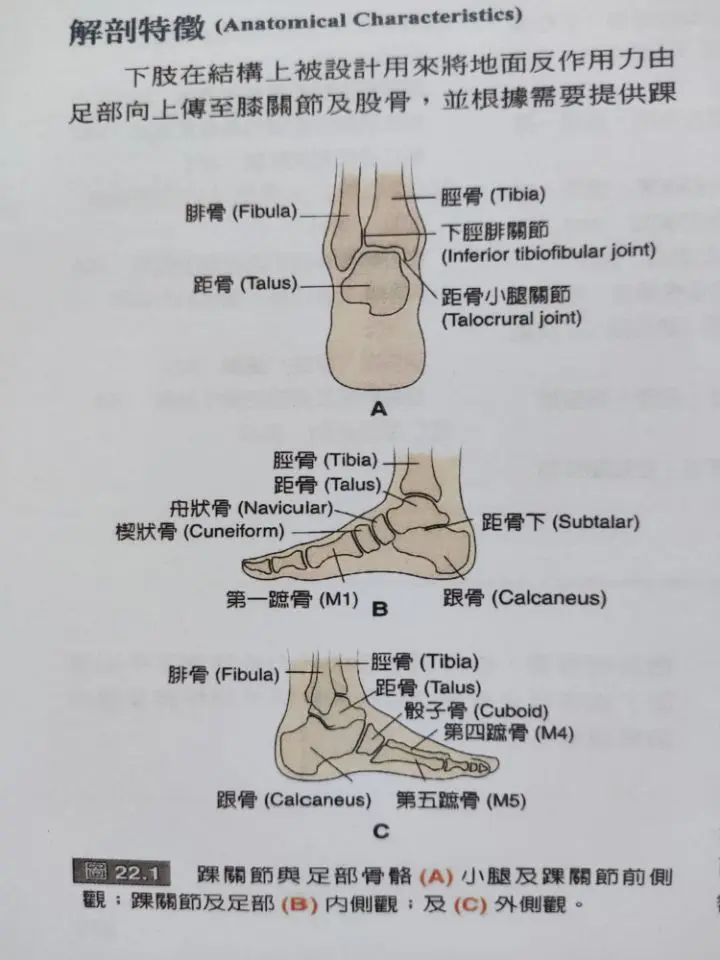

常说的踝关节,只是小腿(胫骨和腓骨)与距骨之间的关节,由胫骨和腓骨远端围成的凹槽容纳距骨,也叫距小腿关节。因为小腿远端这个凹槽的形状限制,距小腿关节的左右活动度是不大的。

而且,距骨上没有任何肌肉附着。脚的活动还要更多的涉及到距骨与跟骨相连的距跟关节,共同来完成足踝的运动。

因为足踝的复杂结构不完全等同于其他关节,它的外展内收被定义为了外翻和内翻,水平旋转则被定义为了外展和内收。